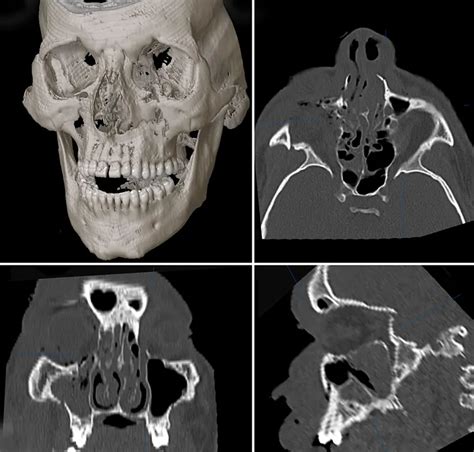

Le Fort fractures are classified into three types, based on the level of the fracture and the extent of facial involvement. Type I Le Fort fractures involve the lower part of the maxillary bone, while Type II and Type III fractures involve progressively higher levels of the face, including the nasal bones, orbits, and zygomatic arches. Accurate diagnosis is critical for determining the most effective treatment approach, and typically involves a combination of physical examination, imaging studies (such as CT scans), and clinical evaluation.

How are Le Fort fractures diagnosed?

+Diagnosis of Le Fort fractures typically involves a combination of physical examination, imaging studies (such as CT scans), and clinical evaluation. Accurate diagnosis is critical for determining the most effective treatment approach.